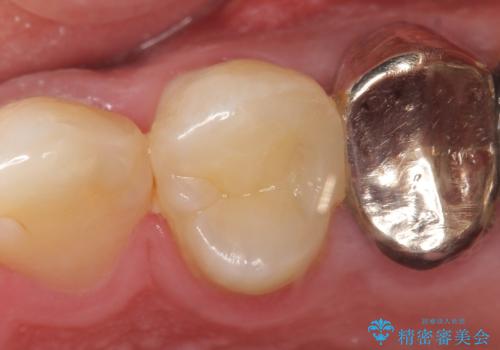

そのため左上4番目の歯は根管治療を行い、歯茎の膿の出口の消失を確認後、オールセラミッククラウンによる補綴を行いました。

今回用いたオールセラミッククラウンはジルコニアフレームという白い素材の上にセラミックを盛っているため、審美性が非常に高いのが特徴です。

また、ジルコニアは人工ダイヤモンドの材料にも使われているほど高い強度を持っており、そのためオールセラミッククラウンは審美性だけでなく、奥歯やブリッジの補綴も可能とするクラウンです。